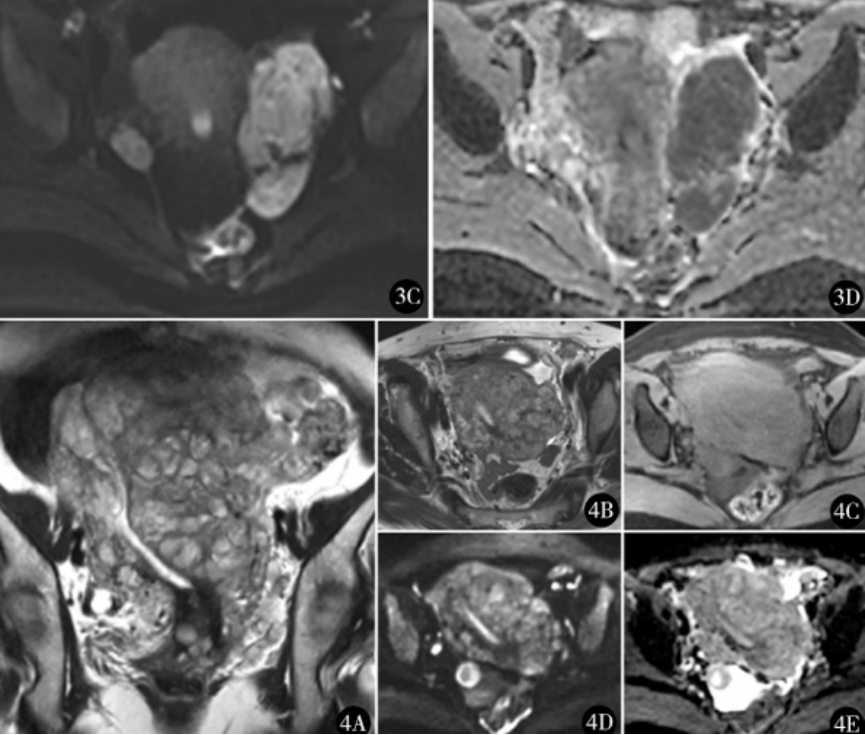

图3 富于细胞性平滑肌瘤(CL)MR平扫:患者33 岁,外院子宫肌瘤剔除术后11个月,发现盆腔包块1个月,行子宫肌瘤剔除术,术后病理富于细胞性平滑肌瘤。 A.轴位T2WI肿瘤为左宫旁卵圆形高信号肿物,边界清晰,未见“蠕虫样延伸” 征;B.轴位T1WI显示肿瘤内少许高信号;C.肿瘤DWI信号增高;D.ADC图为明显低信号,即为DWI明显弥散受限区

图4 静脉内平滑肌瘤病(IVL)MR平扫:患者43岁,扪及下腹部包 块2周,行全子宫和双附件切除术,术后病理为静脉内平滑肌瘤病。 A、B.冠状位和轴位T2WI 肿瘤呈高信号,“蠕虫样延伸”征占据几乎全部子宫肌层,累及宫旁血管;C.轴位T1WI肿瘤未见高信号;D.肿瘤DWI信号增高;E.肿瘤ADC图仍为稍高信号,未见DWI弥散受限。